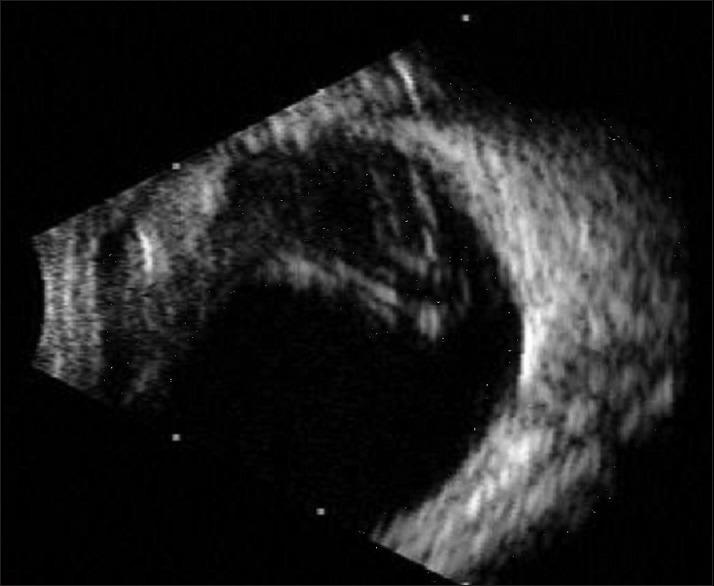

Giant nevus of Ota.

Indian J Ophthalmol. 2015 Jun;63(6):532-3. doi: 10.4103/0301-4738.162607.